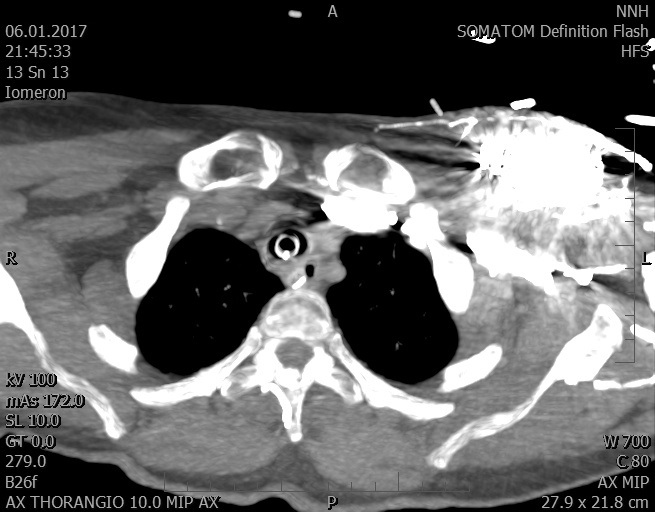

Video 2 - Echokardiograficky byla zjištěna těžká dysfunkce dilatační levé komory s nezvětšenou pravou komorou.Pro nejasnou příčinu zástavy jsme provedli i vyšetření výpočetní tomografií (CT), které vyloučilo plicní embolizaci (série 1 - soubory na konci článku). V den přijetí při přetrvávající oběhové nestabilitě byla nemocná opakovaně defibrilována pro fibrilaci komor se stabilizací rytmu po podání amiodaronu a mesocainu. Dle hemodynamických měření se jednalo o těžký kombinovaný šok. Vstupní laboratorní vyšetření bylo bez větších pozoruhodností. Posléze jsme doplnili anamnézu od příbuzných a zjistili, že pacientka užila do dvou hodin před srdeční zástavou první tabletu amoxicilinu na lehký respirační infekt. Při nevýtěžnosti vstupních vyšetření a nových anamnestických informacích jsme doplnili 14 hodin po kolapsu vyšetření koncentrace tryptázy v séru, která byla extrémně zvýšena (tabulka 2), což nás vedlo k podezření na anafylaxi.